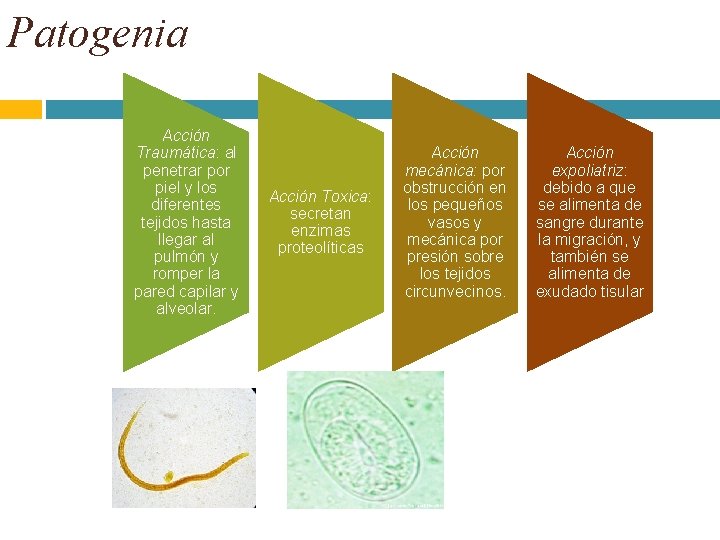

Patogenia Acción Traumática: al penetrar por piel y los diferentes tejidos hasta llegar al pulmón y romper la pared capilar y alveolar. Acción Toxica: secretan enzimas proteolíticas Acción mecánica: por obstrucción en los pequeños vasos y mecánica por presión sobre los tejidos circunvecinos. Acción expoliatriz: debido a que se alimenta de sangre durante la migración, y también se alimenta de exudado tisular